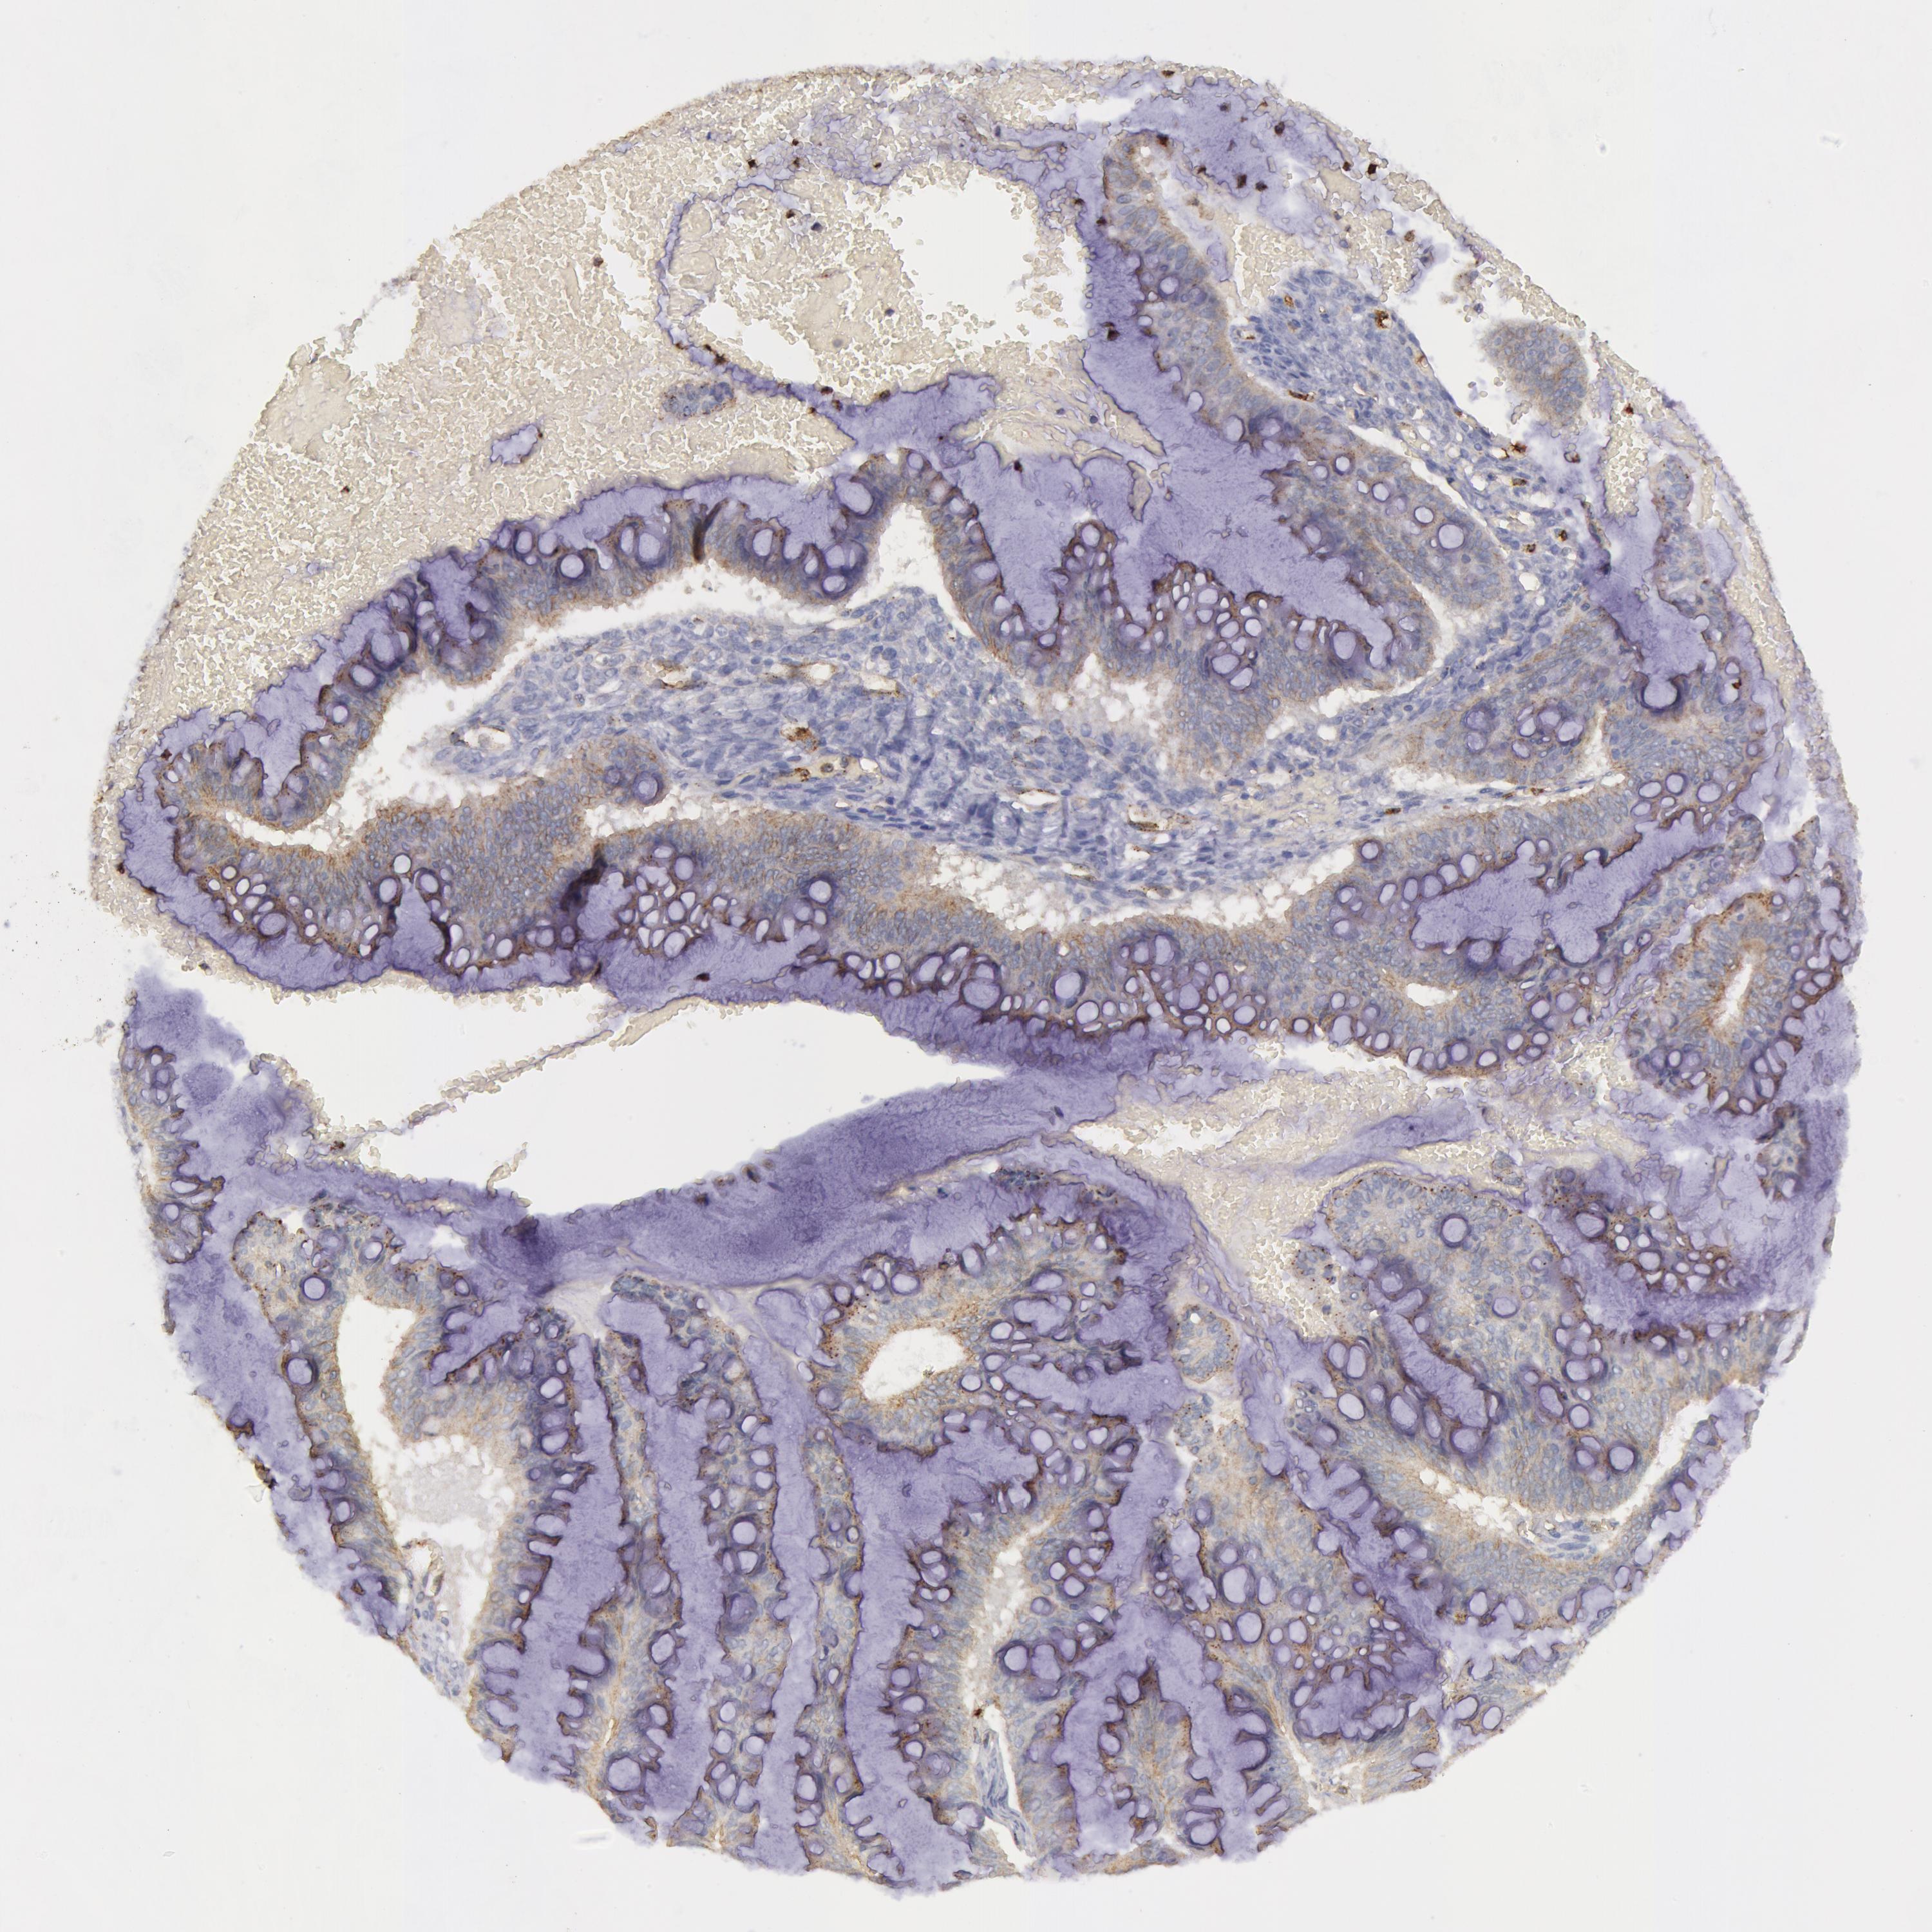

OVARIAN CANCER - Protein expressioni

A mouse-over function shows sample information and annotation data. Click on an image to view it in a full screen mode. Samples can be filtered based on level of antibody staining by selecting one or several of the following categories: high, medium, low and not detected. The assay and annotation is described here.

Note that samples used for immunohistochemistry by the Human Protein Atlas do not correspond to samples in the TCGA dataset.

Antibody stainingi

Antibody staining in the annotated cell types in the current human tissue is reported as not detected, low, medium, or high, based on conventional immunohistochemistry profiling in selected tissues. This score is based on the combination of the staining intensity and fraction of stained cells.

Each image is clickable and will lead to virtual microscopy that enables deeper exploration of all samples and also displays staining intensity scores, fraction scores and subcellular localization as well as patient and tissue information for each sample.

Antibody HPA001396

Antibody CAB004395

Cystadenocarcinoma, mucinous, NOS

Carcinoma, endometroid

Cystadenocarcinoma, serous, NOS

Carcinoma, NOS